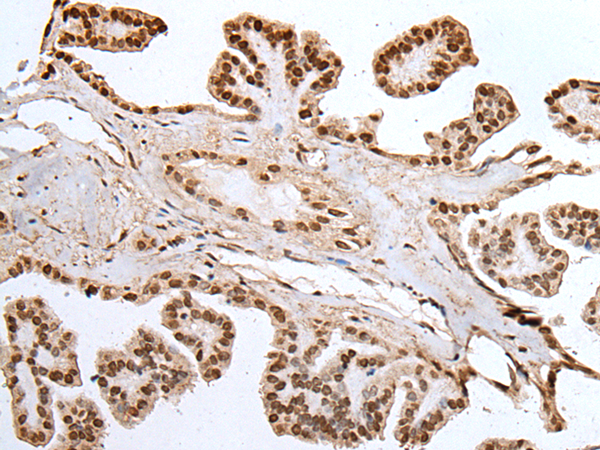

IHC positive control: |

Human esophagus cancer and human thyroid cancer |

IHC Recommend dilution: |

25-100 |